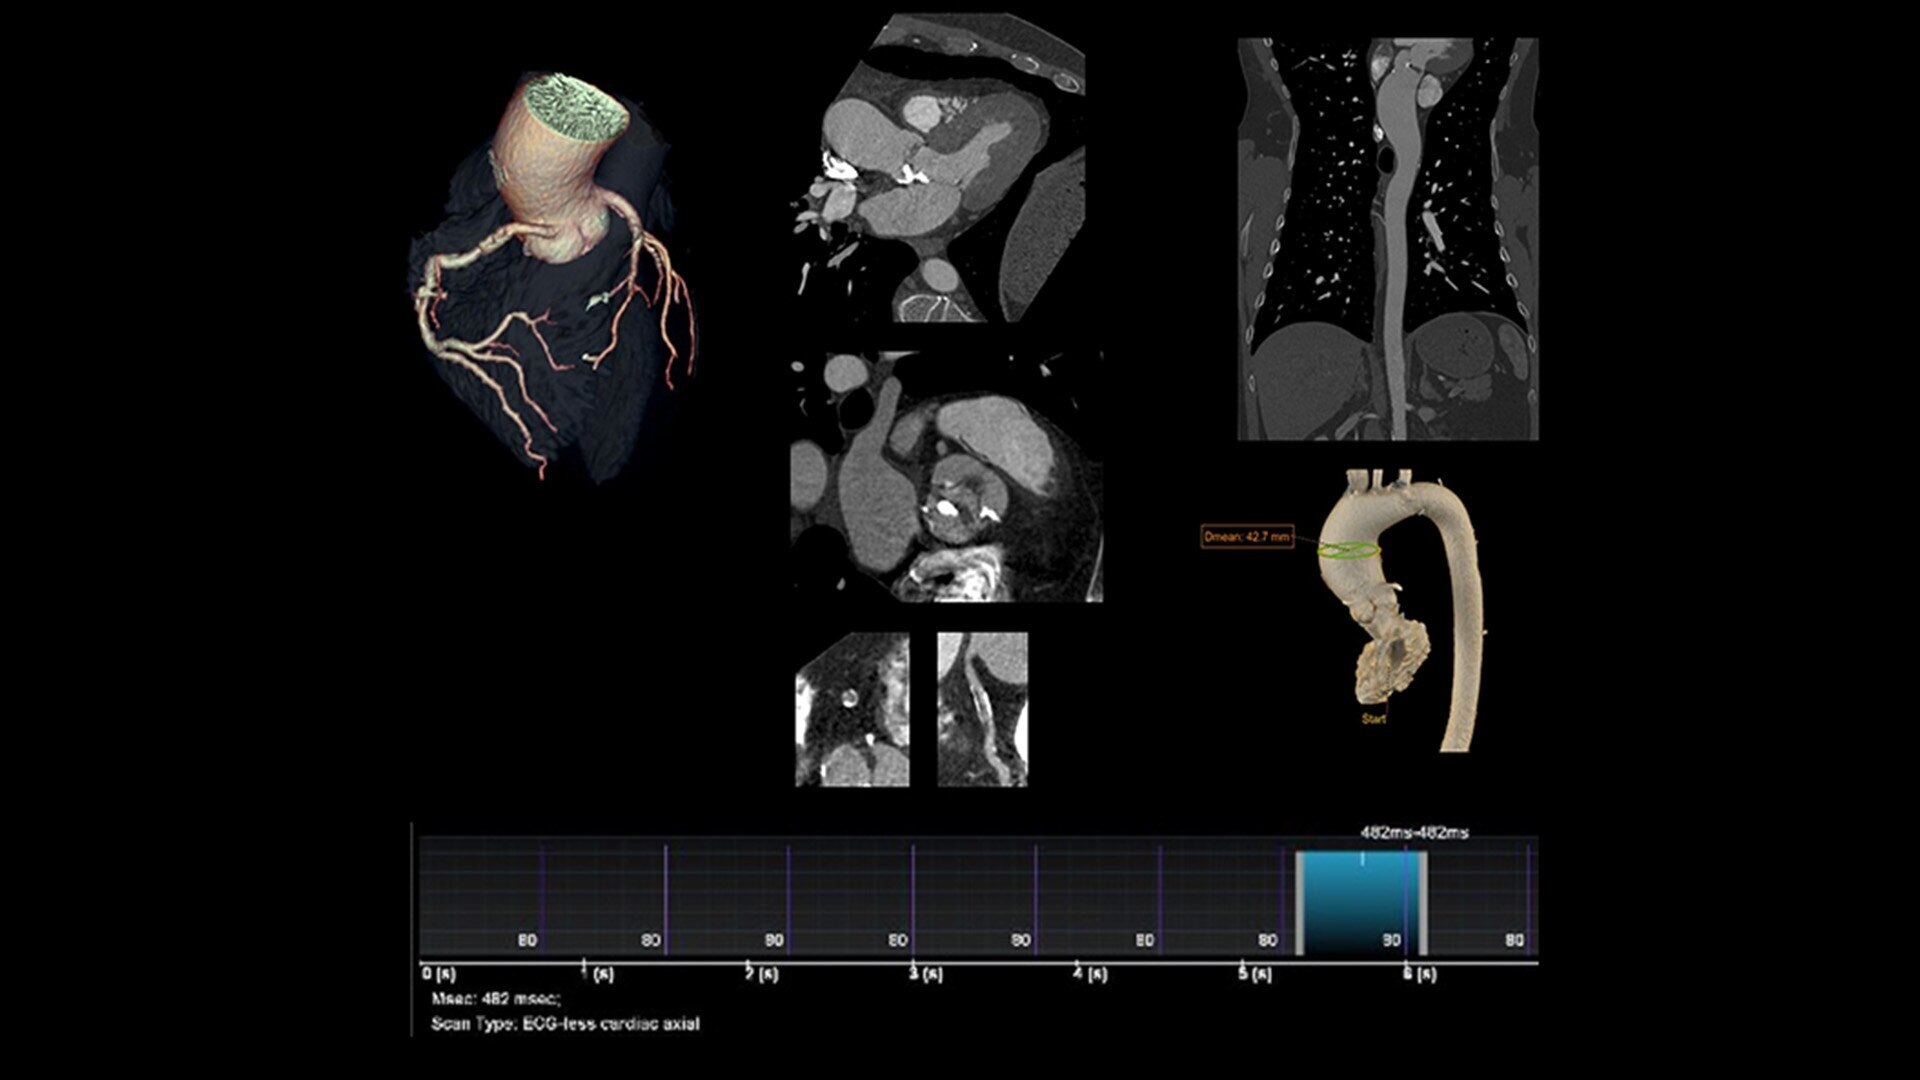

ECG-less Cardiac is a tool that can be utilized in CT examinations where excluding the ECG connection might be desirable, and could help address cardiac exams where patient access and speed need to be prioritized.

These include highly instrumented patients where attaching another ECG device and potentially detaching a diagnostic ECG monitor is not practical. Emergency patients who need access to cardiac evaluation and require fast loading/unloading. In circumstances that prevent obtaining an adequate ECG signal from the patient, and in structural heart assessments.

Powered by breakthrough technology, ECG-less Cardiac CT allows clinicians to streamline the workflow and meet the clinical needs of patients who don’t have a readily accessible ECG